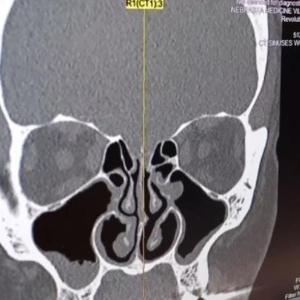

Muitos tipos de exames, como raio-X e ressonância magnética, são essencialmente análise de imagens. E se tem uma coisa que a inteligência artificial sabe fazer bem é ficar de olho em imagens para detectar padrões. Sistemas de inteligência artificial já estão sendo treinados para detectar diferentes tipos de câncer, como câncer de mama, de intestino e de pescoço. Um sistema criado na França e na Alemanha já detecta câncer de pele com 95% de precisão. Já um sistema da DeepMind, do Google, é capaz de detectar com precisão superior a de médicos mais de 50 tipos de doenças dos olhos.

Imagem: iStock

Imagem: Divulgação/Nebraska Medicine